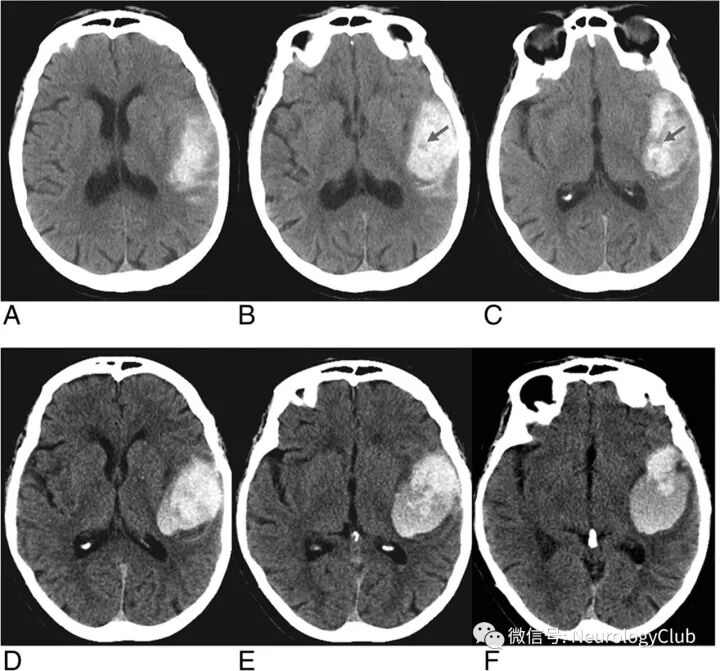

由Al-Nakshabandi于2001年首先描述。定义为CT平扫上2个或以上连续平面高密度血肿内可见低密度区(30-50HU,低或等同于脑实质密度)。近来研究证实,其与脑出血患者血肿扩大相关。

(图6:73岁脑出血患者,最初的头颅CT[A-C]可见左侧顶叶血肿,体积约33ml,其内可见低密度区,即漩涡征;8小时后复查CT[D-F]证实血肿扩大,体积约46ml